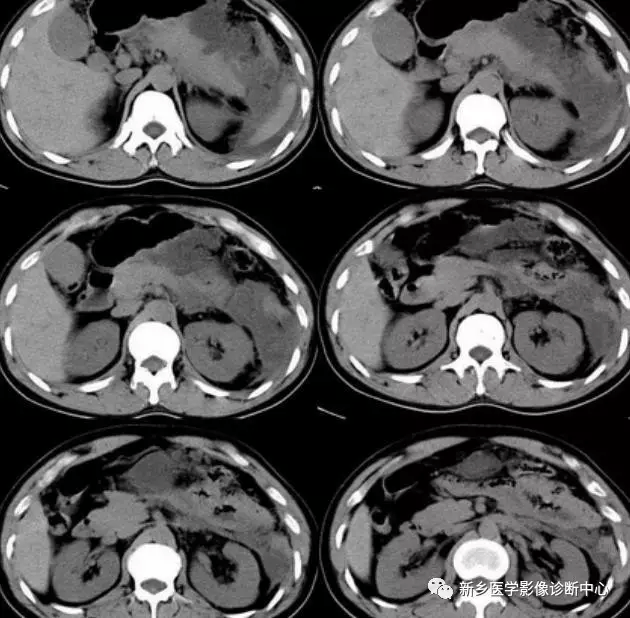

文章图片